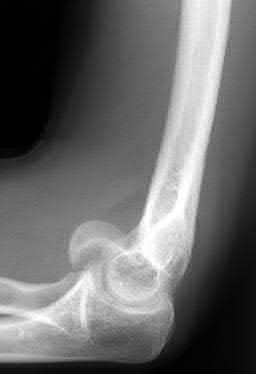

A 55-year-old female falls on an outstretched hand and sustains a distal radius fracture. Radiographs show a fracture of the volar rim of the distal radius with volar subluxation of the carpus alongside the fracture fragment. This fracture pattern is best classified as:

Correct Answer: Volar Barton fracture

Explanation:

A volar Barton fracture is an intra-articular fracture of the distal radius involving the volar rim, accompanied by volar subluxation or dislocation of the carpus. It represents a radiocarpal fracture-dislocation. A Colles fracture is an extra-articular fracture with dorsal angulation/displacement, while a Smith fracture is an extra-articular fracture with volar angulation. A Chauffeur's fracture involves the radial styloid, and a die-punch fracture is an intra-articular fracture of the lunate fossa.